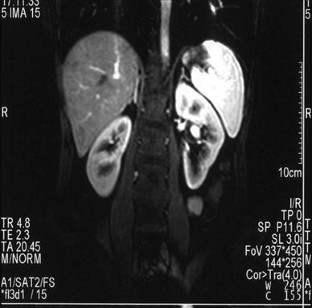

A 40-year-old woman was referred to our department for further investigation of a renal mass identified at an ultrasound (US) examination carried out in a private clinic because of abdominal pain. The mass was oval and hypoechoic, measured about 20 mm in diameter and was located near the left renal sinus; color Doppler showed peripheral blood flow. US examination carried out in our department using different equipment confirmed the presence of the mass but revealed intralesional blood flow suggesting aneurysm. This diagnosis was confirmed at subsequent computed tomography (CT) scanning and magnetic resonance imaging (MRI). The patient refused to undergo surgery and she is currently being monitored and has suffered no sequelae.

Fig. 1